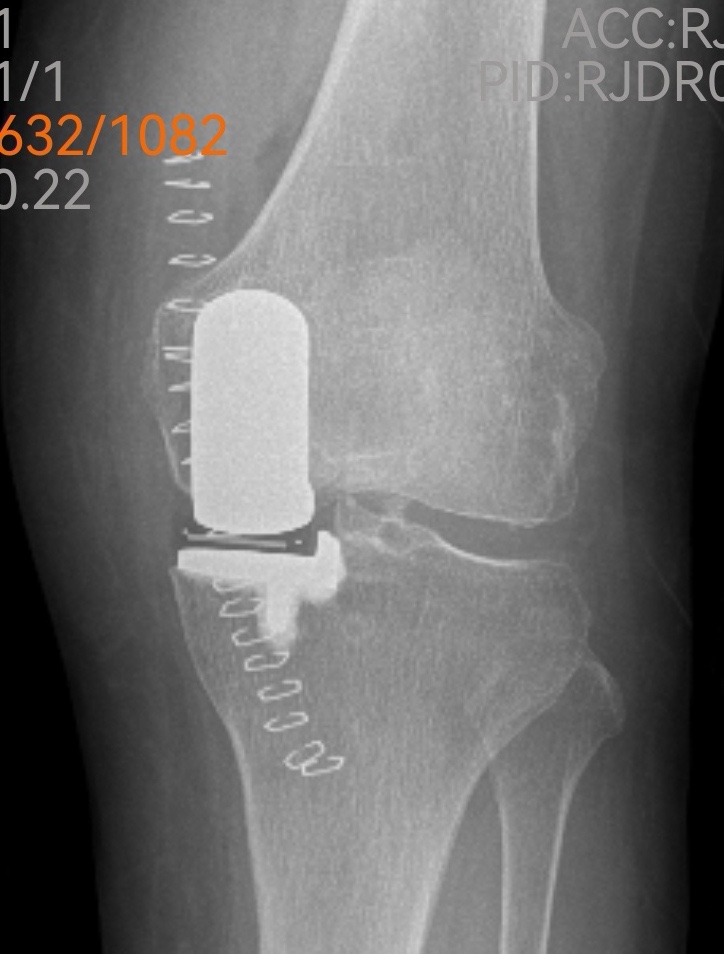

檢查室里,魏海清主任帶領(lǐng)團(tuán)隊(duì)為李阿姨做了詳細(xì)查體。“膝蓋內(nèi)翻畸形,軟骨剝脫,關(guān)節(jié)間隙明顯變窄......”影像學(xué)檢查證實(shí)了醫(yī)生的判斷:左膝關(guān)節(jié)骨質(zhì)增生嚴(yán)重,關(guān)節(jié)面硬化,屈伸活動(dòng)已嚴(yán)重受限。

傳統(tǒng)的全膝關(guān)節(jié)置換固然能解決問題,但創(chuàng)傷較大、恢復(fù)期長。經(jīng)過團(tuán)隊(duì)綜合評估,魏海清主任提出了一個(gè)更精細(xì)的方案:“我們建議行左膝關(guān)節(jié)單髁置換術(shù)。這就像牙齒壞了,我們不必把所有牙齒都換掉,而是只替換損壞的部分。這種手術(shù)只替換磨損的軟骨和部分骨質(zhì),能最大限度保留健康組織。”他拿出膝關(guān)節(jié)模型,耐心地向一家人解釋手術(shù)原理:“您看,膝關(guān)節(jié)分為內(nèi)側(cè)、外側(cè)和髕股三個(gè)部分。您的磨損主要集中在內(nèi)側(cè),所以我們只需置換這一部分。”這種個(gè)體化、精準(zhǔn)化的治療理念,讓原本忐忑的一家人逐漸安心。